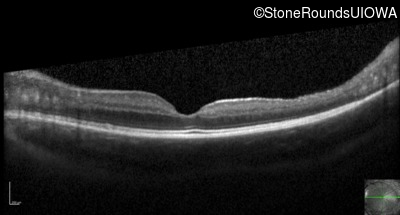

Optical Coherence Tomography - Right - 20/50

Exemplar / OCT Stack

Optical Coherence Tomography - Left - 20/32